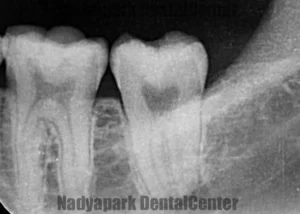

深い虫歯でも神経を抜かずに保存する「バイタルパルプセラピー」の事例

治療1回 + 経過観察2~3回 / 50,000円(税別)リスク・副作用:処置後、一時的に痛みやしみる症状が出ることがあります。神経の状態によっては、後に神経をすべて抜く処置が必要になる可能性があります。